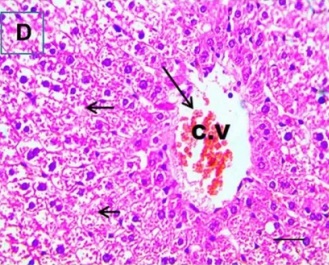

Put the liver tissue section under a microscope, and you can see that cisplatin can cause liver congestion (the blood that should return to the heart is blocked and stagnates in the hepatic veins), cell degeneration (vacuoles appear, which is the earliest change in cellular injury), apoptosis and necrosis, but these conditions can also be alleviated by using Ganoderma lucidum.

Figure 2 Effects of cisplatin and Ganoderma lucidum on hepatocytes